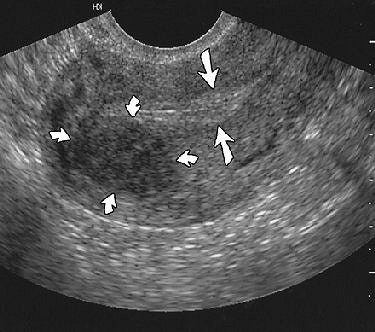

![]() |

| Endometrial polyp in 24-year-old woman. Sagittal sonogram of uterus showing normal-appearing endometrium (straight arrows) measuring 8 mm and posterior uterine leiomyoma (curved arrows). Laifer-Narin S, Ragavendra N, Parmenter EK, Grant EG, "False-Normal Appearance of the Endometrium on Conventional Sonography: Comparison with Saline Hysterosonography," (AJR 2002; 178:129-133). |